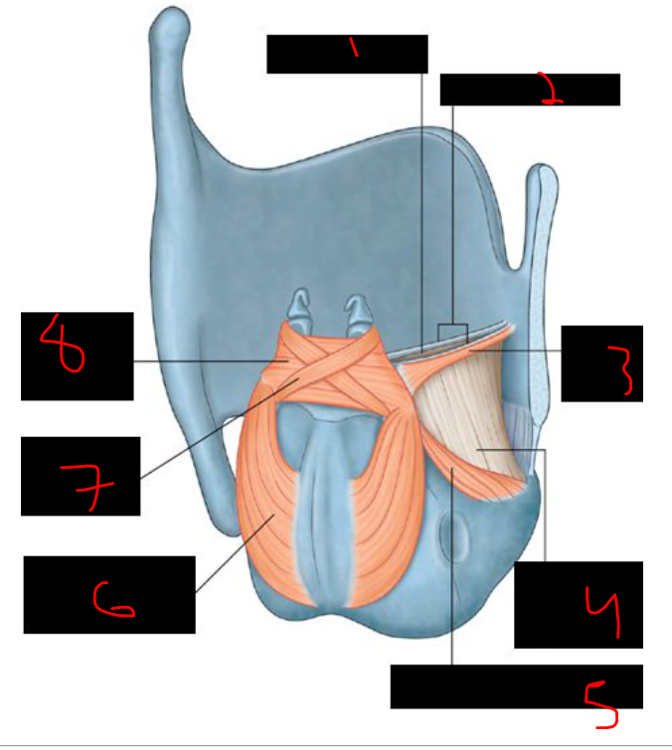

43

card image

What is 7?

pterygopalatine raphe

44

What is 8?

stylohyoid ligament